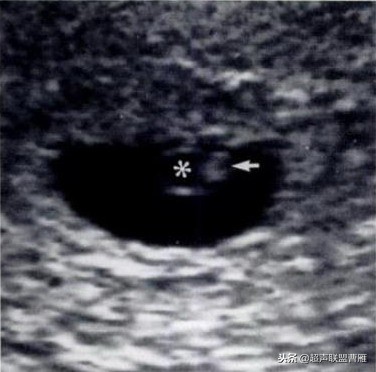

· 正常情况下,卵黄囊中央表现为无回声,周边为厚薄均一、边界清晰的环形高回声。

· 正常卵黄囊内径一般在3-5mm,妊娠第5-10周逐渐增大,而10周后逐渐减小,一般12周前消失。

· 当妊娠囊平均直径在5-6mm时,经阴道超声即可发现卵黄囊

· 通常认为,妊囊>8mm时,应当看到卵黄囊